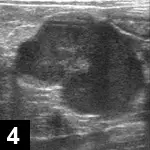

Mesenteric lymphadenopathy (Figure 4)

Figure 4. Abdominal ultrasound from a cat with FIP (non­effusive). A large, well-defined, irregularly marginated, 3-cm hypoechoic mass in the midabdomen (most likely a mesenteric lymph node) is present.